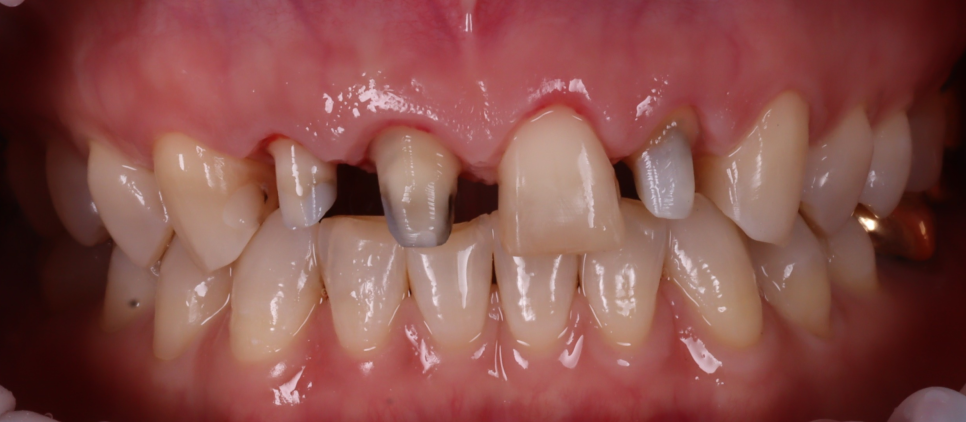

앞니 3개는 크라운이었는데 사이는 원래 치아이다 보니 시간이 지나면서 자연치아의 변색과 마모로 도드라져 보이는 상황이었습니다.

색상이 고르지 않게 보이는 것이 가장 고민이셨는데요.

가운데 보철이 안된 치아는 살짝 앞으로 돌출되었더라고요.

이 상태에서 레진으로 덧붙이면 치아를 덜 깎을 수는 있지만 더 튀어나와 보일 수 있어요.

레진은 ‘치아를 거의 삭제하지 않는 치료’라는 분명한 장점이 있지만, 모든 경우에 항상 가장 최선의 선택이라고 보기는 어렵습니다.

그래서 이 치아는 레진이 아니라 라미네이트가 더 자연스러운 결과를 만들 수 있는 상황이라고 설명드렸어요.

치료 방법을 결정할 때 가장 우선되어야 할 기준은 재료가 아니라, 치아가 놓여 있는 위치와 방향입니다.